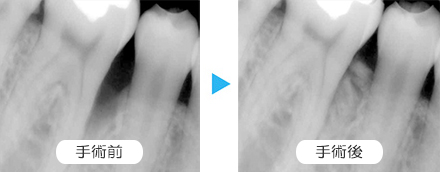

歯周病が進行していて、歯石除去、クリーニングが終わっても、まだ病状が安定しない方への歯ぐきの手術です。

骨がないところに足す処置をしたり、再生処置をしたりと、歯の保存のための手術です。